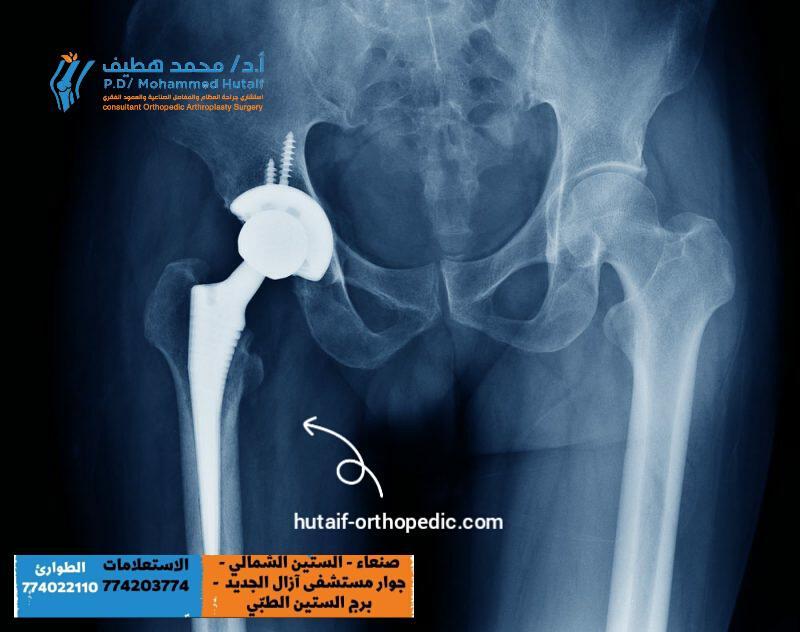

عندما يعاني الشخص من ألم شديد في مفصل الورك، قد يكون الحل الأمثل هو الجراحة. فالجراحة تعد من أكثر الخيارات فعالية…

إذا كنت تعاني من مشكلات في مفصل الفخذ، فقد يكون العلاج الوحيد هو استبدال المفصل. ولكن ما هي أنواع مفصل الفخذ المتاحة؟ و…